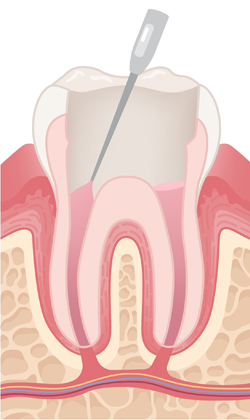

필요 시 치아를 지지할 기둥을 넣고, 접근 통로로 만든 구멍을 충전재로 메워 치아의 구조를 안정적으로 회복시킵니다.

약해진 치아를 보호하기 위해 맞춤 제작된 크라운을 씌워 강도와 기능을 회복시키며, 장기적으로 안전하게 사용하도록 마무리합니다.